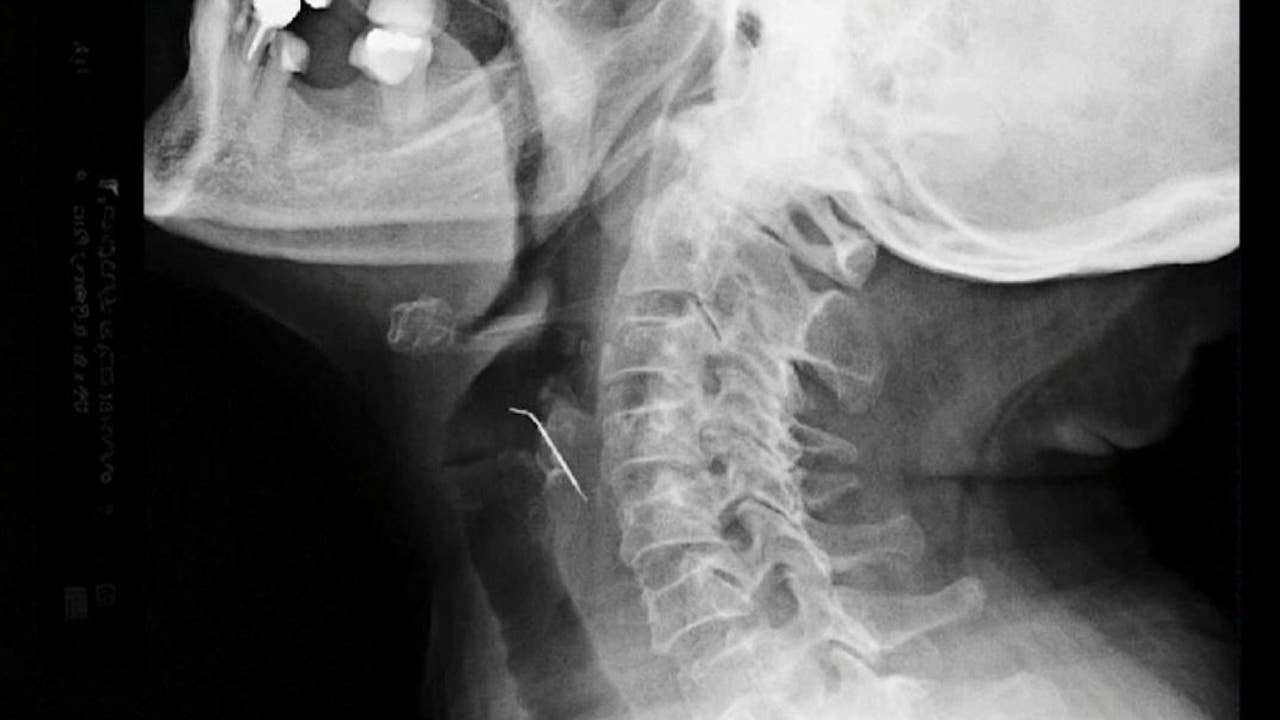

X-ray of nail stuck in throat of patient. (COURTESY: ESSALUD)

The woman soon fell ill and began vomiting blood. After being taken to an emergency room, doctors discovered that the nail was piercing one of her carotid arteries, which help supply oxygen and blood to the brain.

Tello's x-ray images showed the nail protruding into her throat. The woman, who now has a neck scar, has healed since then.